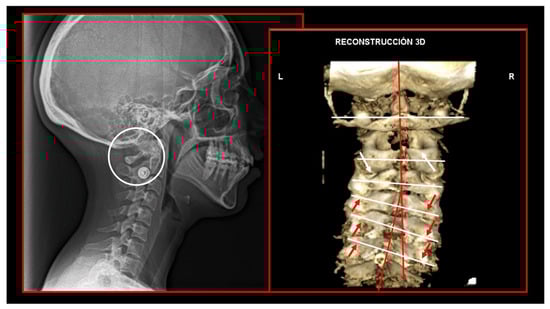

10.1. Neck X-ray

10.2. Computed Tomography of Cervical Spine